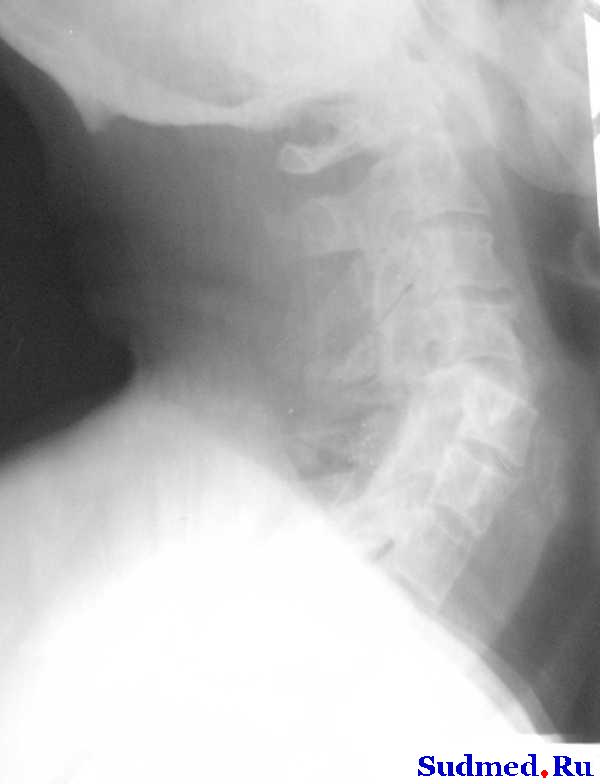

описание снимков такое : На рентгенограммах шейного отдела позвоночника в 2-х проекциях определяется вывих С4 кзади на ½ диаметра тела позвонка, со сдавлением позвоночного канала на ¾ диаметра. Признаки остеохондроза шейного отдела позвоночника С2-С3, С№-С4, С4-С5, С 5-С6 2 степени.

В протоколе операции повреждение задней связки не описано. На вскрытии тмо не вскрыта, спинной мозг с кровоизлиянием размягчен, задняя продольная связка(идет по задней поверхности тела позвонков в спиномозговом канале - ? если не путаю) отслоена от тела 4 позвонка.

рентген, наконец-то выложил

Эскизы прикрепленных изображений

Судебная медицина - Прикрепленное изображение

с меньшими шумами

Судебная медицина - Прикрепленное изображение Судебная медицина - Прикрепленное изображение